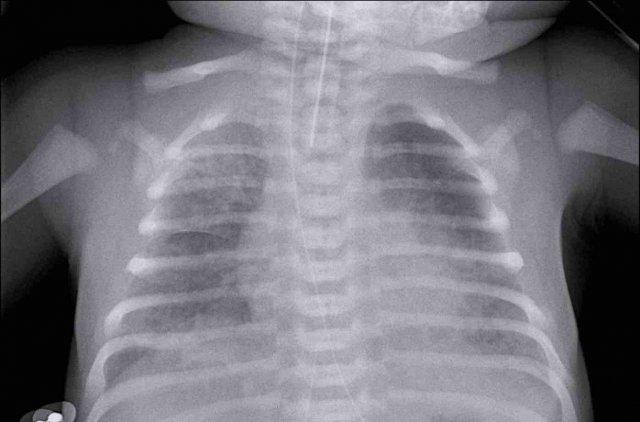

33 tuần + 5 tuần tuổi thai, ngày đầu tiên.

Nhìn vào hình ảnh trước.

Những phát hiện là gì?

Findings:

- Intubated

patient. - Good position of endotracheal tube (ETT). Hyperinflation.

- Symmetric

granular opacifications with air bronchograms. - Definition of heart and vessels

is diminished.

This is a typical case of RDS.